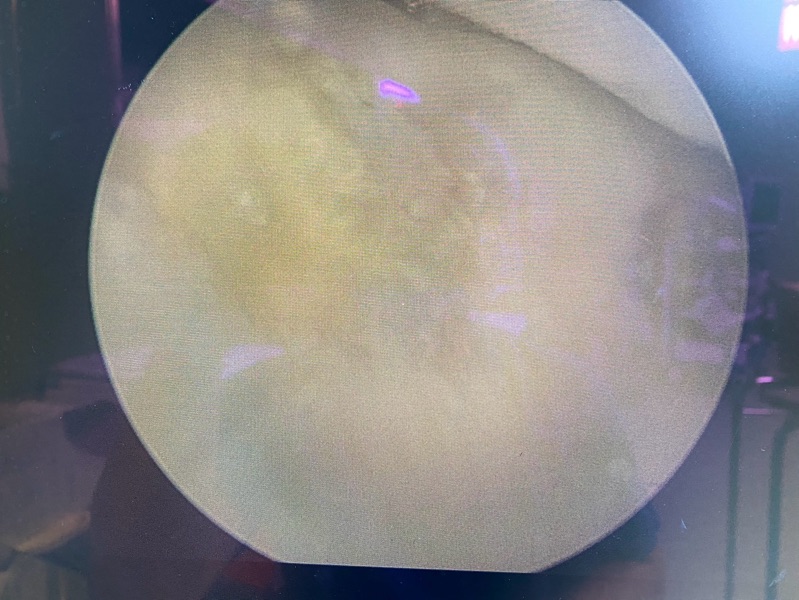

一位二十多歲年輕女性,因籃球運動膝蓋撞擊,導致滑車軟骨局部剝離。經MRI檢查確認為 ICRS Grade III 軟骨缺損。考量患者不願意接受多次手術,我選擇使用一次性自體軟骨修復技術。術後半年,疼痛大幅改善,膝蓋屈伸順暢,MRI 追蹤亦顯示缺損區域已填補良好。

上圖:關節鏡像顯示軟骨損傷